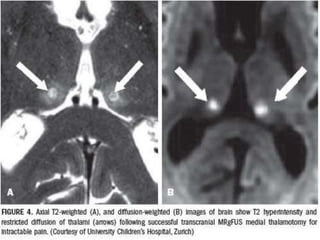

•2. SURGICAL RESECTION

OF THALAMUS.

•THALAMOTOMY /

•SUBTHALAMIC RESECTION